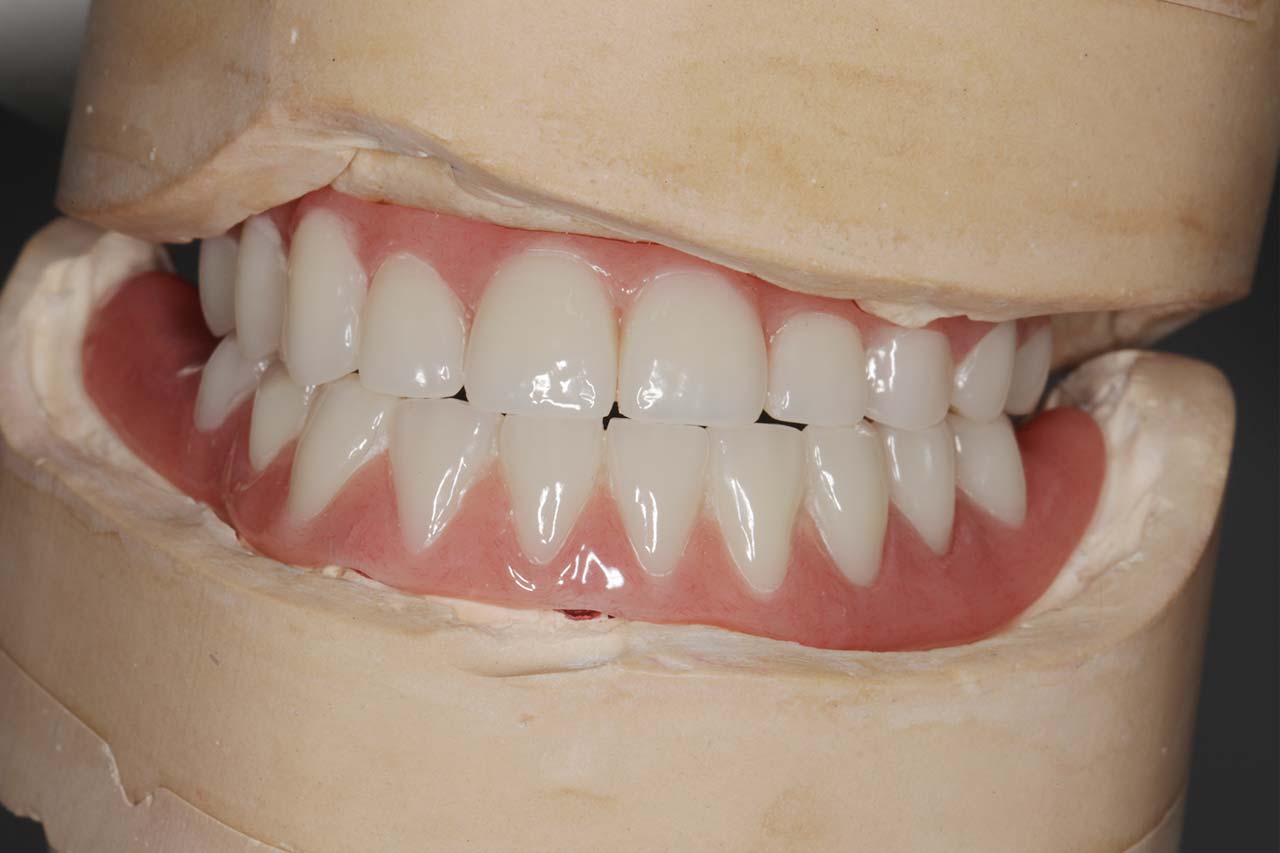

„Implantatprothetik – Unterschiede zwischen kompromittierten und gesunden Patienten“

Prof. Dr. Sven Reich